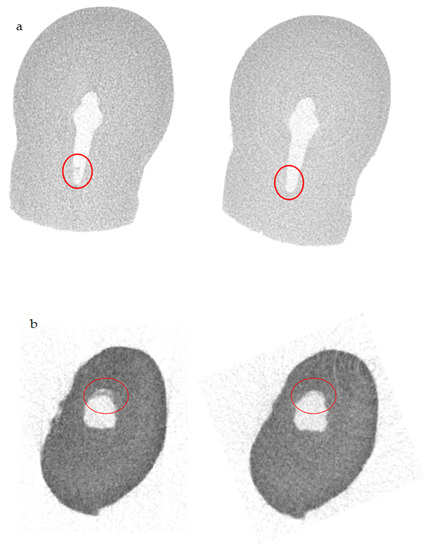

- Electric Current Activation Group (n = 5) (EB Group): The specimen was irrigated with 5 mL of NaOCl at 5.25% preheated using TruNatomy irrigation needle (Dentsply Sirona). For the electric current activation, ElectroBond (Patent No. WO03/002014 PCT/IB02/02565, Rome, Italy) was used. ElectroBond delivered a direct current (DC) between the endodontic dentin (working as cathode) and the irrigating solution (working as anode) [14]. The tested ElectroBond automatically induced an electric flow over 20 μA throughout the irrigating solution through the endodontic dentine during the application procedure. To permit electricity conduction under in vitro conditions, the tooth to be tested was surrounded by a transmitting medium inside the ProTrain (Figure 1).

| SkyScan 1072—ISS | Before Irrigant Activation | After Irrigant Activation |

|---|---|---|

| Volume of shaped root canal (mm3) | 7.3745 ± 0.0008 | 7.3745 ± 0.0008 |

| Volume of AHTD (mm3) | 0.3162 ± 0.0009 | 0.0289 ± 0.0008 |